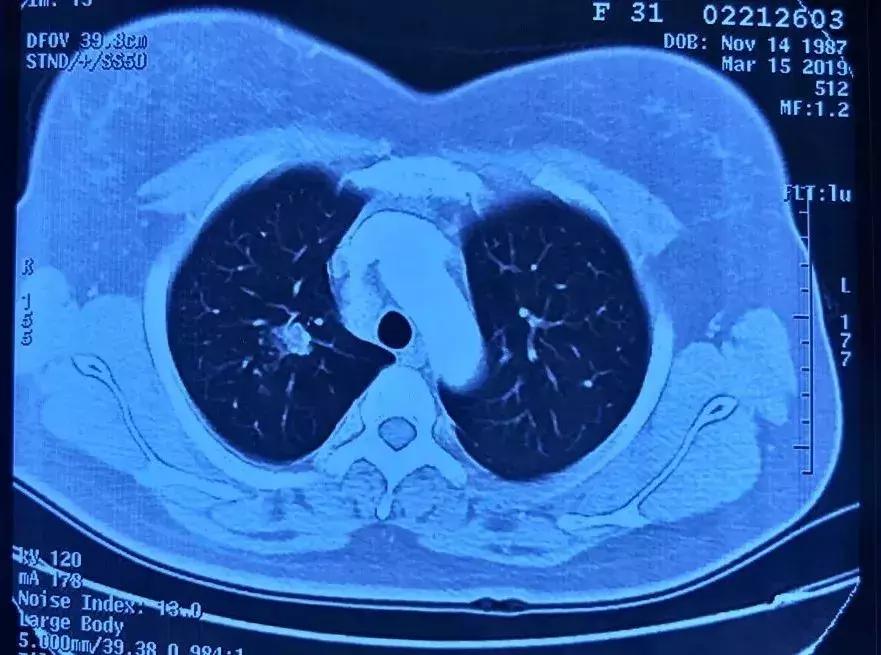

支修益教授介绍,首次做胸部低剂量螺旋CT发现肺小结的,一般医生会根据结节的部位、大小、形态、密度,边缘有没有毛刺、分叶,是否有引流支气管、血管征,中心有没有空洞等综合考虑。一般我们根据结节大小将结节分为肺结节、肺小结节和微小结节,常见以下几种:

3、疑似肺癌的肺结节:支修益教授谈到,如果是首次胸部CT检出「疑似肺癌的肺小结节」,也需要定期复查,根据医生的判断决定复查间隔时间,「患者」也不要过度惊慌,胸外科医生也不要立即外科手术干预,因为有些良性肺小结节只是「穿着坏人衣服」疑似早期肺癌而已。即使通过随诊观察决定手术干预,最后病理报告真的是早期肺癌,也不会因为这3个月或半年的观察期就发生转移而影响预后。

对于第三种疑似早期肺癌的肺小结节,观察期到底是三个月、半年还是一年?支修益教授解释,还是要根据肺结节的部位、大小、形态和密度等结节特征综合判断并决定其复查间隔时间。近年来,临床上还有很多双肺多发肺小结节,更不能急于外科手术治疗啊!